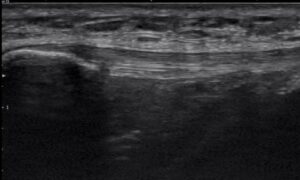

One of the most valuable tools I use in my practice is diagnostic musculoskeletal ultrasound.

Unlike static imaging, ultrasound allows us to:

- Visualize the tendon in real time

- Assess its structure and quality

- Correlate what we see with your symptoms and movement

This helps answer critical questions:

- Is the tendon acutely irritated or more chronically changed?

- Is there a mismatch between your symptoms and the tissue’s appearance?

- How does the tendon respond during movement?

This level of detail allows for a much more precise and personalized treatment plan.